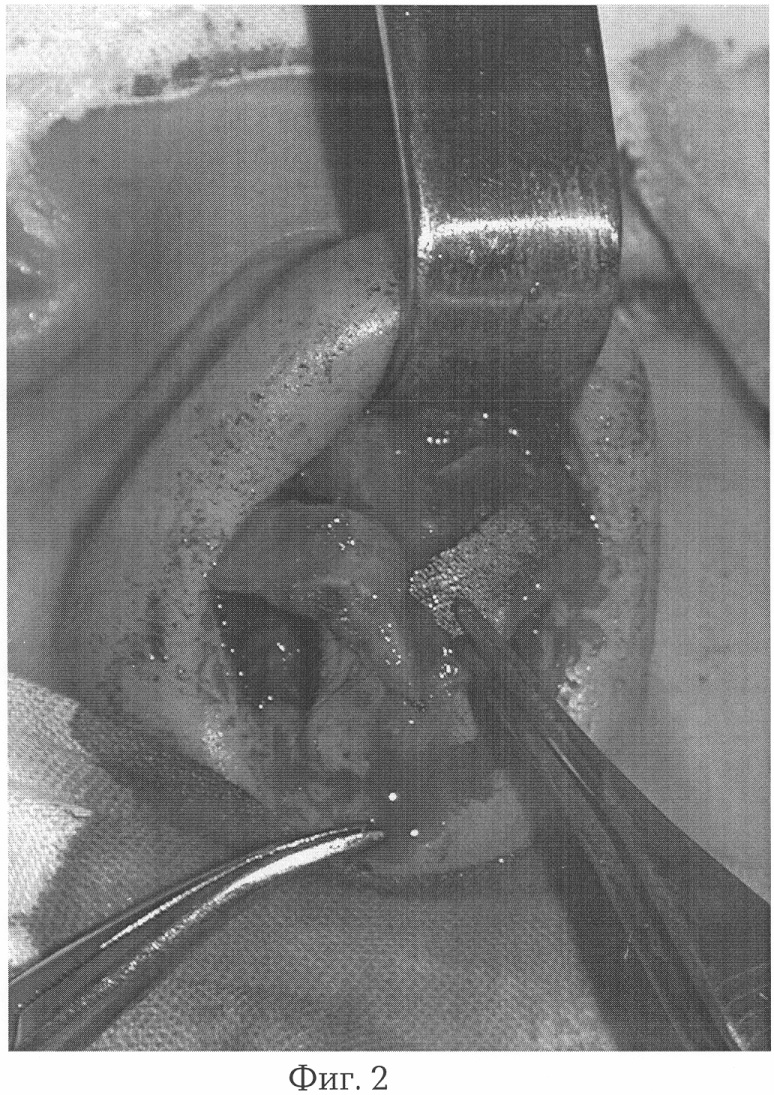

Предлагаемый способ поясняется фотографиями, где на фиг.1 изображен вид больной С. до операции, на фиг.2 – пористый имплантат из никелида титана установлен в область дефекта крыла носа, на фиг.3 – вид больной С. через 3 года после операции.

Пример. Больная С., 26 лет, обратилась в клинику с жалобами на затруднение носового дыхания. Из анамнеза выяснено, что 2 года назад получила удар в область носа, через 4 месяца оперирована по поводу деформации кончика и спинки носа, после чего отмечает нарушение носового дыхания. При осмотре определяется сужение левого носового хода за счет деформации четырехугольного хряща, проляпс левого крыла носа во время вдоха, обусловленный изъяном латеральной ножки большого крыльного хряща. После анестезии проведены трансколлумальный и левосторонний краевой разрезы в области носа, мягкие ткани отслоены и мобилизованы вверх, обнажены хрящевой отдел кончика носа, наружная поверхность латеральной ножки большого крыльного хряща и добавочные хрящи, нижне-наружный край грушевидного отверстия на стороне поражения. Определяется дефект латеральной ножки левого большого крыльного хряща, обусловленный резекцией во время предыдущей операции. Разделены купола и долечки средних ножек больших крыльных хрящей, в проекции хрящевого изъяна сверху установлен имплантат в виде сверхэластичной пористой пластины из никелида титана толщиной 0,15 мм, шириной 4 мм, повторяющий наружный контур хрящевого скелета крыла носа с опорой на край грушевидного отверстия в проекции дистального края добавочных крыльных хрящей и между средними ножками больших крыльных хрящей, который фиксирован никелидтитановой нитью толщиной 60 мкм к остаткам хрящевого скелета крыла носа, кожно-жировой лоскут уложен на место, рана ушита. Послеоперационный период протекал без осложнений. При осмотре через 3 года форма носа удовлетворительная, функциональных нарушений со стороны носа не отмечено.